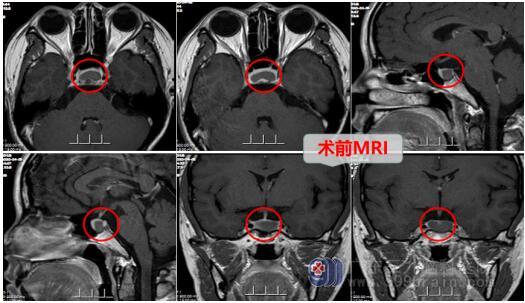

34岁的吴女士一向身体健康,但一年前体检意外发现鞍区病变,她在网上不停搜索相关信息,越看越害怕。为了尽快治疗,于是来到广东三九脑科医院神经外十科就诊,查垂体MR示“垂体中份(前后叶间)异常信号灶,考虑Rathke囊肿可能”。

入院后完善相关检查,主管医生邓心情详细告知术前注意事项,可能会发生的并发症以及手术方案,可以不用开颅采用微创手术,即经鼻腔进入,术后不用填塞纱布,恢复快。家属明白手术风险后签字同意,择期进行了内镜经鼻鞍区rathke囊肿切开引流术,术程顺利,术后病人很快苏醒,没有发生原来担心的并发症,无尿崩,离子正常,鼻腔不用纱布填塞,病人呼吸顺畅。